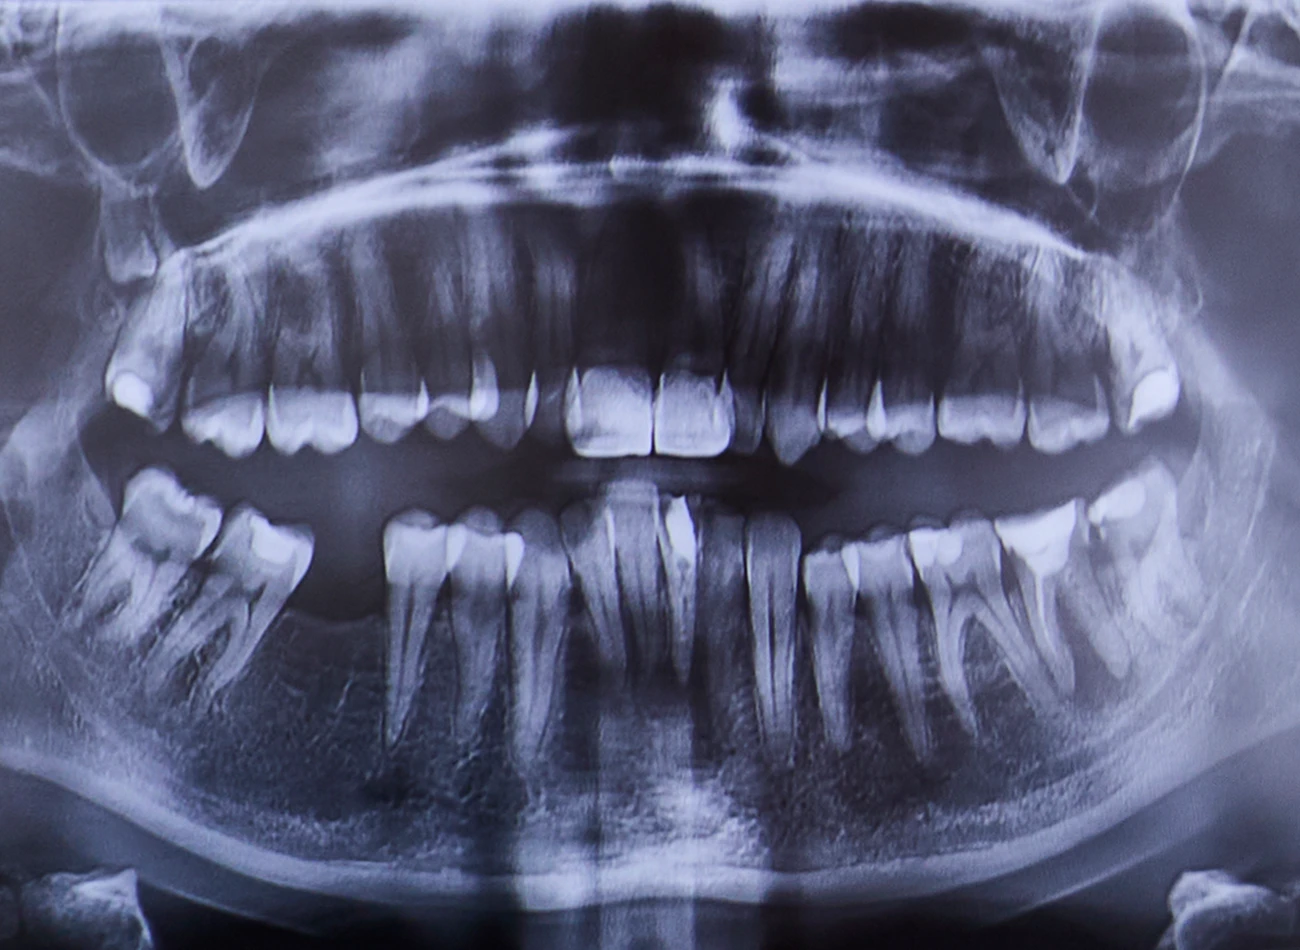

Präzise 3D-Diagnostik mit minimaler Strahlenbelastung.

Trotz ihrer enormen Leistungsfähigkeit ist die Strahlenbelastung bei der DVT vergleichsweise gering und liegt deutlich unter der von konventionellen CT-Aufnahmen. So profitieren Patientinnen und Patienten von einer exakten Diagnostik bei gleichzeitig hoher Sicherheit.